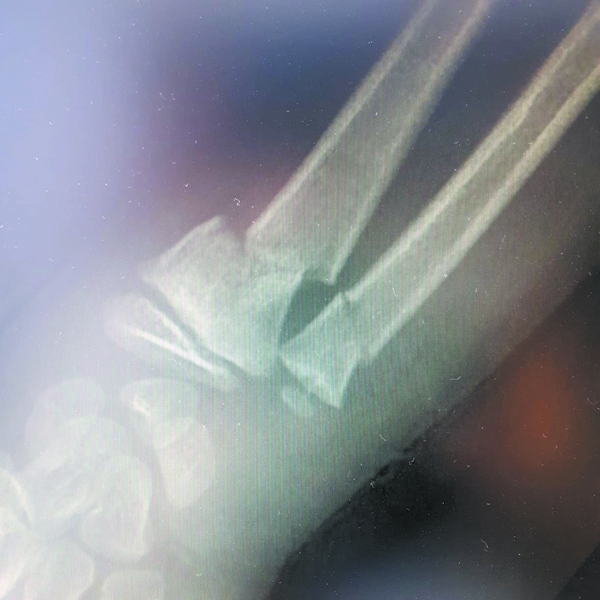

Врачи диагностировали закрытый перелом нижней трети костей правого предплечья

Спустя первые 3 дня после наложения тугой повязки жанаозенским “лекарем” цвет кожи на руке стал резко меняться. “Обеспокоенная” мать снова пошла за советом к целителю, но тот отправил мальчика домой, успокоив, что всё идет как надо. В жанаозенскую городскую больницу ребенка привезли только спустя 2 недели. Врачи сразу же направили его в областную многопрофильную детскую больницу в Актау. Врачи диагностировали закрытый перелом нижней трети костей правого предплечья, тромбоз сосудов правого предплечья и некроз правой кисти. Срочно было принято решение ампутировать правое предплечье и кисть.